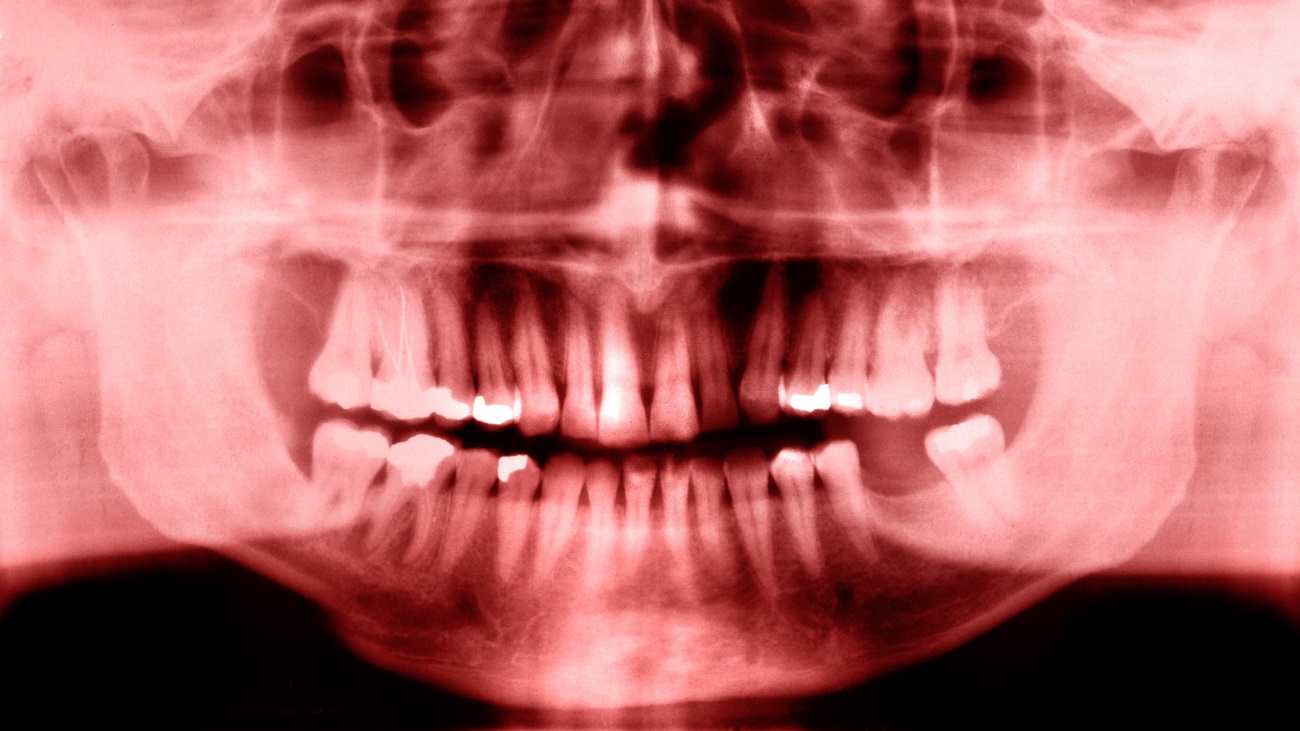

Een mensenleven is, als het goed is, lang. En er kan in die tijd van alles gebeuren waardoor je een tand of kies moet missen. Als de tandarts dan vervolgens aankomt met bruggen, plaatjes of implantaten denk je al snel: kan dat nou niet anders? Nou, dat kan misschien binnenkort anders. In Japan gaan, na een reeks succesvolle proeven op muizen en fretten, tests van start met behandelingen die ook bij mensen nieuwe tanden kunnen laten ontstaan.

Tijdens het onderzoek, dat van september tot augustus 2025 zal plaatsvinden in het Kyoto University Hospital, worden dertig mannen in de leeftijd van 30 tot 64 jaar behandeld die ten minste één kies missen. Ze krijgen intraveneuze injecties toegediend om USAG-1 uit te schakelen.

Na deze eerste fase van 11 maanden gaan de onderzoekers het medicijn testen op patiënten tussen 2 en 7 jaar die door een aangeboren afwijking ten minste vier tanden missen; een aandoening die naar schatting bij 1 procent van de mensen voorkomt.